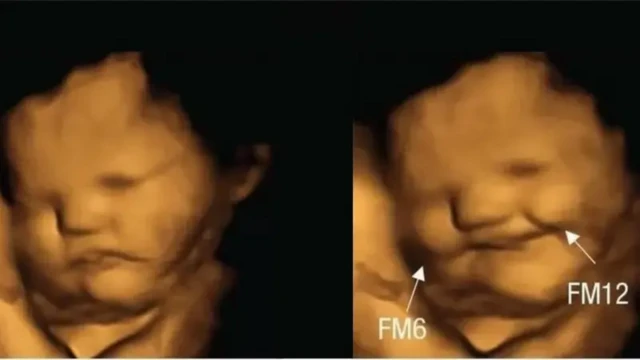

Xigashada Sawirka, FETAL AND NEONATAL RESEARCH LAB, DURHAM UNIVERSITY

'Baruurta ku dhex jirta Baruurta' Waa Cillad ku Dhalasho

Caafimaad ahaan marka loo hadlayo, ilmo sheey oo kale ah marka laga helo minka haweenayda uurka leh, waxaa loogu yeeraa 'uurjiifta ku jirta uurjiifta'; laakiin sida ilmaha ma weynaanayso ama korayso.

Sida daraasad lagu daabacay mareegta rasmiga National Library of Medicine, 'uurjiifta ku jirta uurjiifta' waa ku dhalasho xaalad naadir ah. Uurjiifta aan dhamaystirnayn ayaa ku sameysanta jirka ilmaha.

Uurjiifta waxaa ay badanaa usoo muuqataa sida buro oo kale xiliga lagu guda jiro heerka koriinka ee uu sameynayo ilmo galeenka, laakiin waxaa ay u kortaa si ka duwan sida uu ilmuhu u koro.